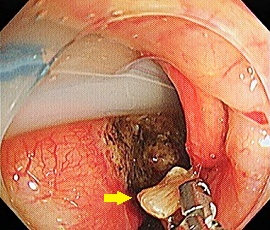

[咽頭腔外魚骨異物] 手術:内視鏡的粘膜下層剥離術(異物除去)

内視鏡画像